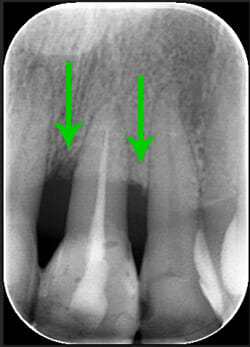

Endorale prima e dopo la cura della parodontite

Con terapia parodontale microinvasiva: si noti la ricrescita naturale dell’osso e del tessuto parodontale.